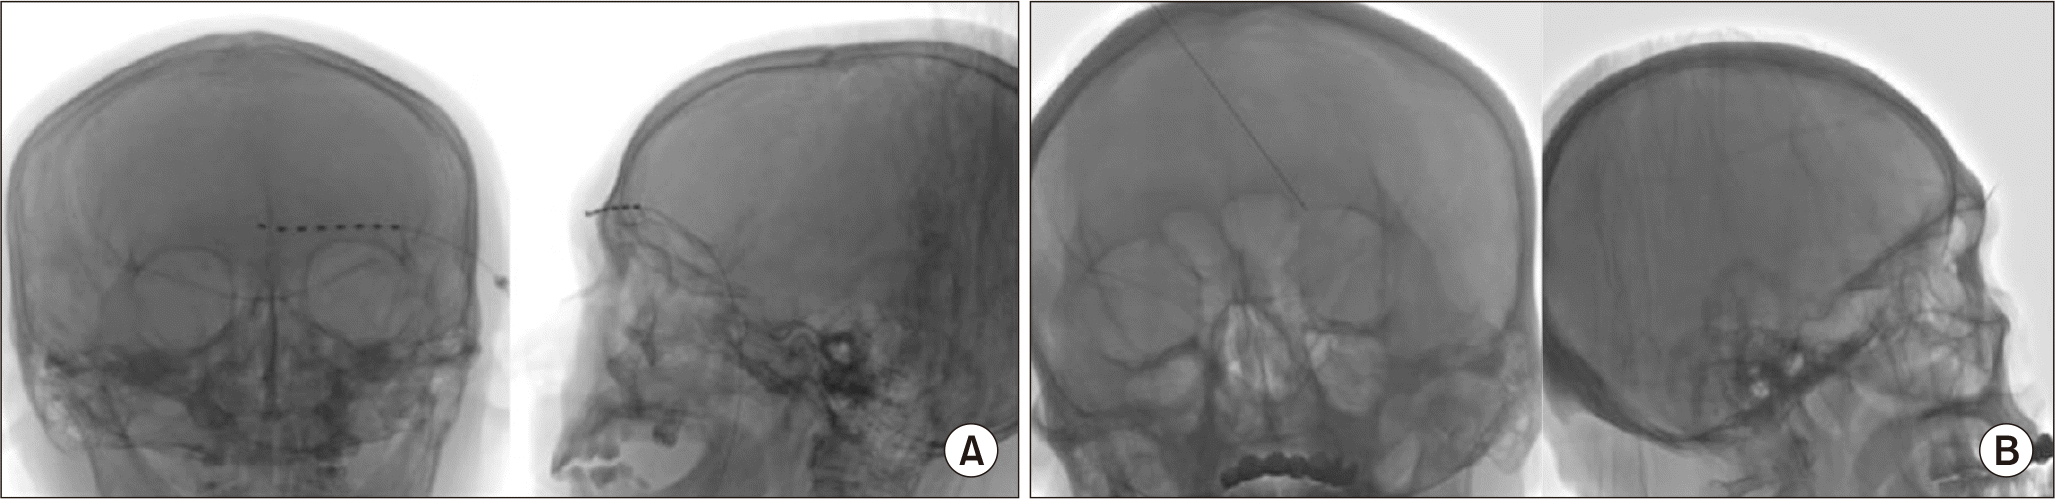

The patients were placed in a supine position with a pillow under the scapula to tilt the head back. The head was tilted to the opposite side of the surgery and a film was applied to protect the eyes. The skin entry point was the intersection point 2–3 cm lateral of the outer canthus and 2–3 cm above the lateral canthus. After sterilization and anesthesia with 1% lidocaine at the level of the supraorbital ridge and superficial temporal fascia, a 14-gauge Tuohy needle was inserted transcutaneously and directed along a semilunar trajectory towards a supra-periosteal tissue plane located above the eyebrow. X-ray-guided transcranial surface puncture was performed to the cranial midline (Fig. 1A). A stimulation lead with eight electrodes (Model 3873; Medtronic) was inserted through the Tuohy needle under X-ray with the tip of the lead crossing the midline. The patient was returned to the ward and the neurostimulator (Model 37022; Medtronic) was connected to implantable electrodes after the anesthetic had worn off. The stimulation amplitude was 0.5–5.0 mV, 0–3 (–), 4–7 (+) for all patients. The stimulation frequency was 40–100 Hz and the pulse width was 500 µS. The electrical stimulation voltage was adjusted according to the pain severity and the patient’s tolerance to electrical stimulation. The duration of the stimulation was 10 days.

The application of supraorbital nerve PRF in treating acute HZO patients was applied under local infiltration anesthesia. Using ultrasound, a radiofrequency needle with a 5-mm exposed tip was inserted into the supraorbital notch. Upon reaching the expected position, a high-frequency (50 Hz, 500 μs width, < 0.2 V) stimulation test was conducted, which could induce forehead pain. Subsequently, the X-ray was used to confirm the placement of the needle tip (Fig. 1B). The PRF parameters were set at PRF mode (42°C, 2 Hz) for 600 seconds.

Fig. 1

Representative images of the PNS and PRF procedure. (A) Representative images of the PNS procedure. (B) Representative images of the supraorbital nerve PRF procedure. PNS: peripheral nerve stimulation, PRF: pulsed radiofrequency.